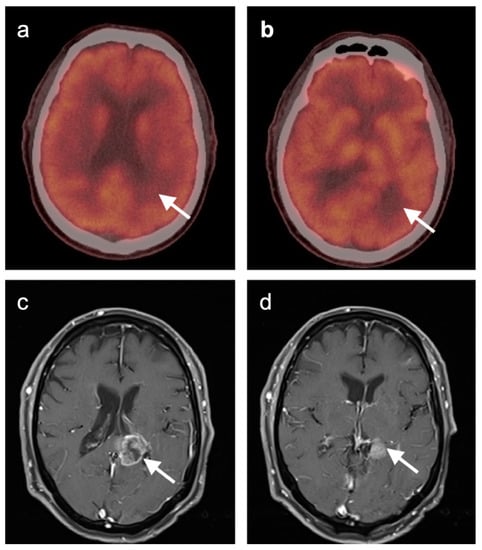

3.3. Primary Brain Tumors

3.6. Response to Therapy

3.5. Brain Metastases